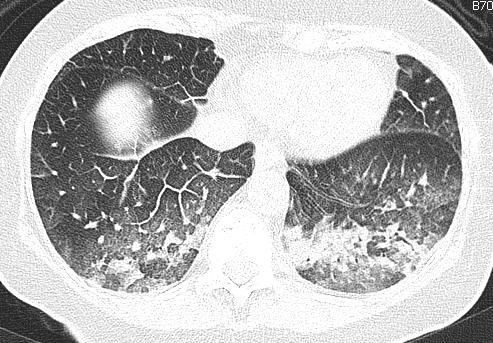

ground-glass opacities mixed with consolidation; typically the GGO forms the edge of the opacities

spared costophrenic angles

prominent septal lines only in the area of the GGO indicating, the subacut phase, when resolution begins; opacities are mainly gravity dependent

partial resolution in a few days